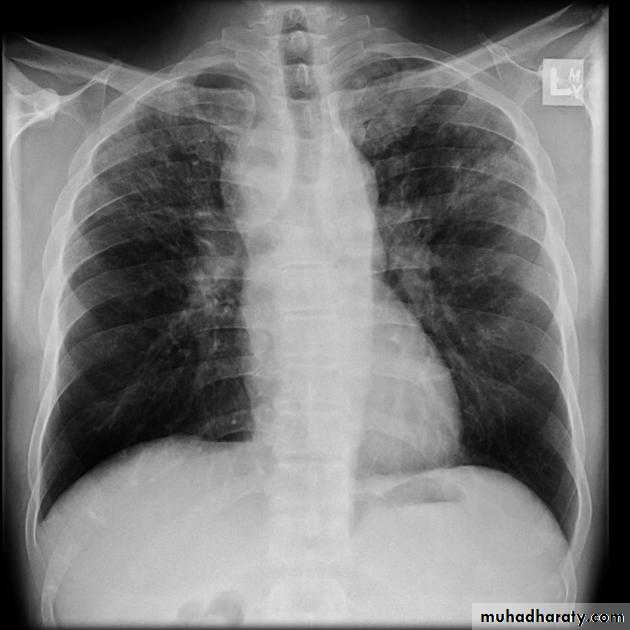

pneumothorax

When air enters the pleural space, the parietal and visceral pleura separate making the visceral pleura visibleThe thin white line of the visceral pleura is called the visceral pleural white line

You must see the visceral pleural white line to make diagnosis of pneumothorax!

Simple pneumothorax

In a simple pneumothorax, there is no shift of the heart or mediastinal structures (trachea)

Air in left hemithorax balances the air in the right hemithorax

Tension pneumothorax

Progressive loss of air into pleural space causing a shift of the heart and mediastinal structures away from side of pneumothoraxOpposite lung is compressed

Respiratory function severely compromised